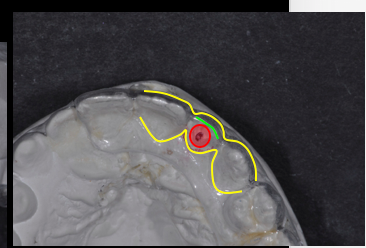

The following is the mapping technique for a partially edentulous presentation:

- Obtain diagnostic casts of the edentulous space.

- Measure (with mm calipers) 1.5 mm from each cervical aspect of the adjacent teeth and mark the cast. (Overall space available must be 6.5 mm minimum.)

- Mark the center of the ridge between the adjacent teeth on the cast.

- Duplicate the model.

- Create a diagnostic wax-up for the edentulous space.

- Fabricate a clear acrylic implant placement guide from the wax-up model.

- Place a guide on the mapped model and drill a hole through the guide into the stone at the center mark (a 2.0 mm diameter hole is ideal for the surgeon’s initial twist drill).

- Provide the surgeon with the implant guide prior to implant placement appointment.